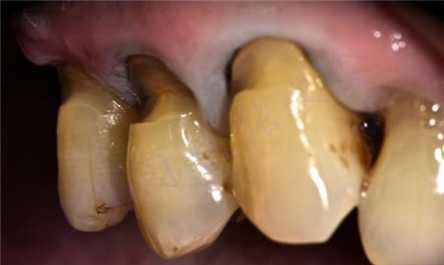

楔状缺损

又称牙颈部非龋性缺损,常表现为尖牙、前磨牙唇、颊面的牙颈部楔形缺损。发病率随年龄而增高。病因有磨损、酸蚀、应力等因素。常伴 有牙本质过敏、牙龈退缩,严重者可出现牙髓暴露甚至出现牙折。